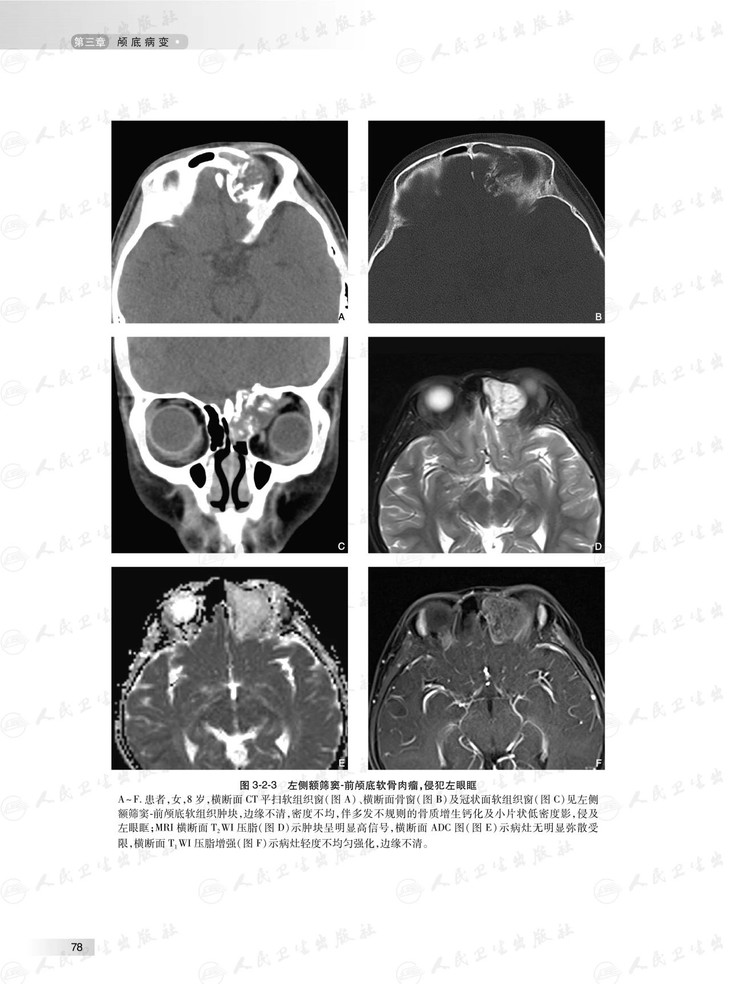

本书根据头颈部影像临床工作场景,对头颈部影像学征象或表现进行系统讲解和分析,头颈部包括的部位多,结构复杂细微,病变种类繁杂,每个部位的影像学征象和表现各有特点,据此,本书按照颅底、耳部、鼻腔与鼻窦、眼球与眼眶、咽喉部、口腔、颌面部、舌骨上颈部间隙和舌骨下颈部间隙等部位各成一章。头颈部外伤性病变有其自身特点,故独立成章。本书图文并茂,具有全面、系统、简洁和清楚的特点。